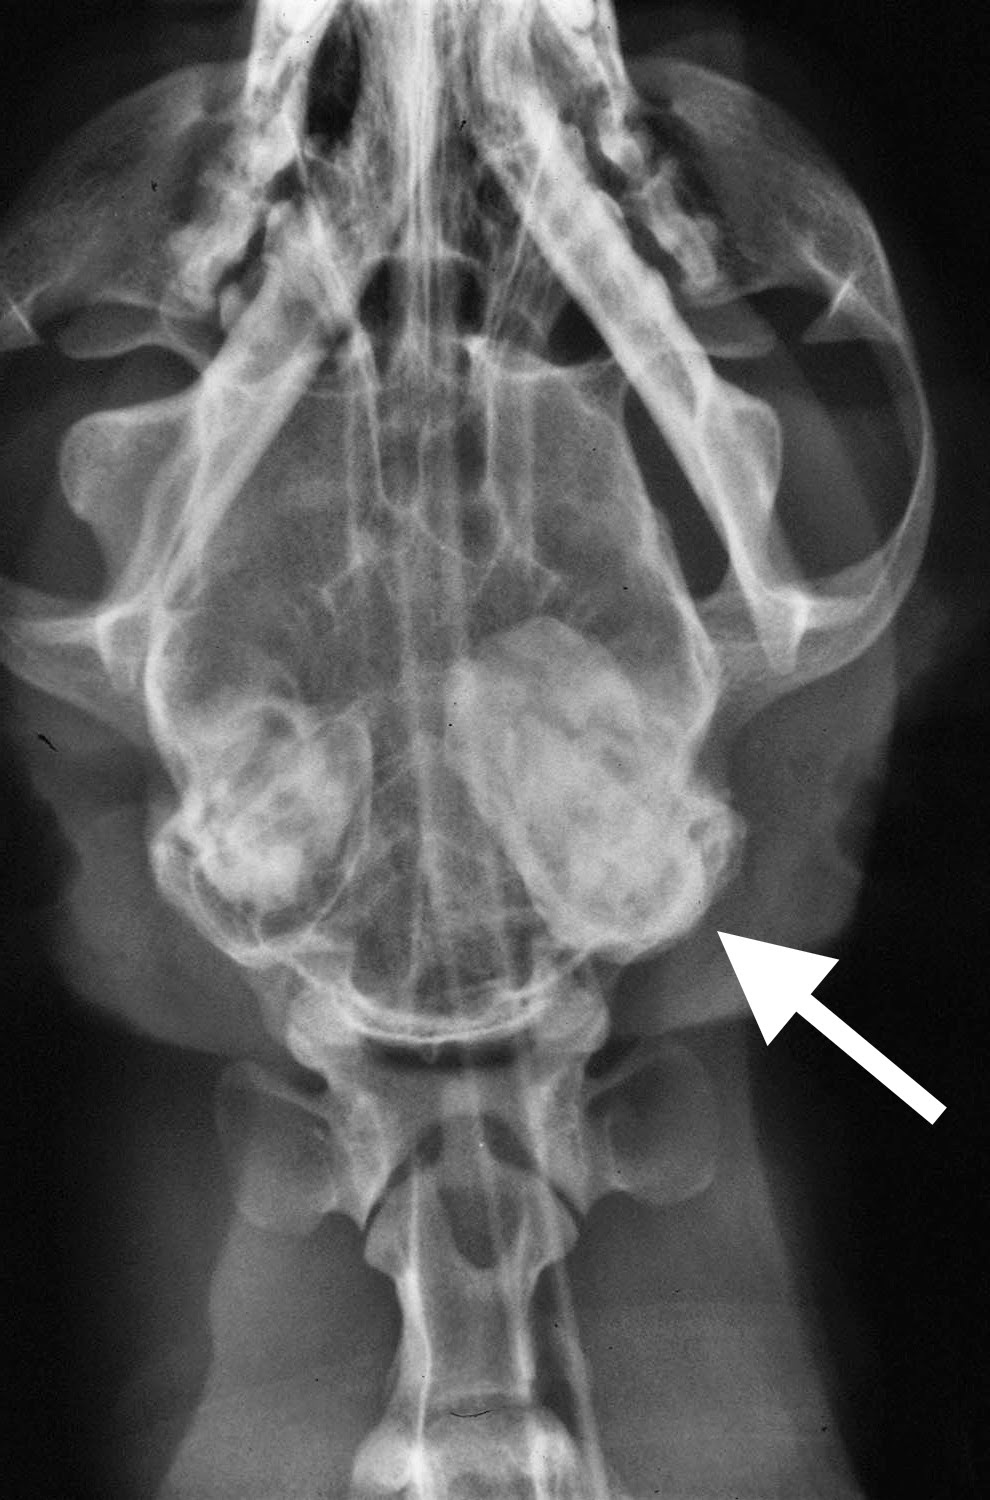

Cat X-Ray Skull . Common and important indications for radiography of the skull include nasal. in the feline, the main indications for skull radiography include trauma, nasal discharge (acute, chronic,. • during each imaging series of the skull, one of the projections. the skull is the most complex and specialized part of the skeleton; the author prefers the dorsoventral view over the ventrodorsal view, as it is easier to position the skull flat on. indications for skull radiography. It is a challenging region to evaluate with. obtain diagnostic skull radiographs for several reasons: the anatomy of the skull and nasofacial area of the dog and cat is complex, with cavities, sinuses, mandible, maxilla, dental.

Cat X-Ray Skull the author prefers the dorsoventral view over the ventrodorsal view, as it is easier to position the skull flat on. the skull is the most complex and specialized part of the skeleton; obtain diagnostic skull radiographs for several reasons: • during each imaging series of the skull, one of the projections. in the feline, the main indications for skull radiography include trauma, nasal discharge (acute, chronic,. indications for skull radiography. the anatomy of the skull and nasofacial area of the dog and cat is complex, with cavities, sinuses, mandible, maxilla, dental. the author prefers the dorsoventral view over the ventrodorsal view, as it is easier to position the skull flat on. Common and important indications for radiography of the skull include nasal. It is a challenging region to evaluate with.

Veterinary Key Points Nasopharyngeal Polyps in Cats Key words Cat X-Ray Skull It is a challenging region to evaluate with. indications for skull radiography. the author prefers the dorsoventral view over the ventrodorsal view, as it is easier to position the skull flat on. • during each imaging series of the skull, one of the projections. obtain diagnostic skull radiographs for several reasons: the anatomy of the skull. Cat X-Ray Skull.

CAT TRAUMA Cat X-Ray Skull obtain diagnostic skull radiographs for several reasons: • during each imaging series of the skull, one of the projections. the author prefers the dorsoventral view over the ventrodorsal view, as it is easier to position the skull flat on. indications for skull radiography. in the feline, the main indications for skull radiography include trauma, nasal discharge. Cat X-Ray Skull.

Feline Skull Radiographs Cat X-Ray Skull obtain diagnostic skull radiographs for several reasons: It is a challenging region to evaluate with. the skull is the most complex and specialized part of the skeleton; indications for skull radiography. in the feline, the main indications for skull radiography include trauma, nasal discharge (acute, chronic,. • during each imaging series of the skull, one of. Cat X-Ray Skull.